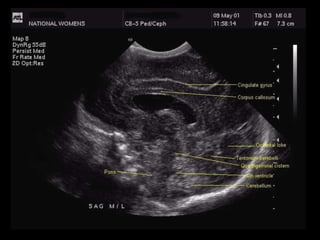

Midline Sagittal

This identifies useful landmarks.

The cerebellar vermis shows up as an echogenic image in the posterior fossa.

The 4th ventricle sits in front of this.

The cisterna magna sits below the cerebellar vermis and is not very echogenic.

The corpus callosum is seen sweeping from anterior to posterior with the cingulate gyrus above

and parallel to it.

The parieto-occipital sulcus is seen well above the posterior fossa.